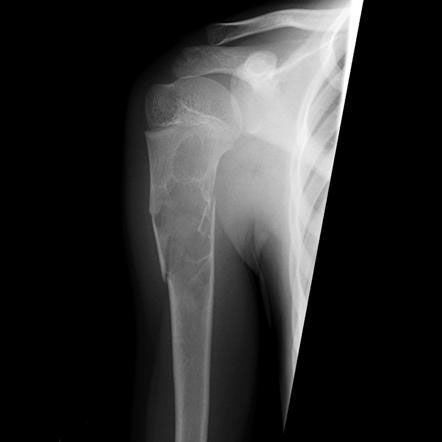

Bone tumors are rare lesions. A large part of these tumors are benign lesions, and they often occur by chance during radiological examinations for another reason. As a complaint, they usually show swelling and pain. Rarely, it is diagnosed after causing a fracture in the place where it was. Osteoid osteoma, osteochondroma (exostosis), enchondroma, non-ossifying fibroma, eosinophilic granuloma, simple bone cyst, fibrous dysplasia and intraosseous lipoma/ganglion are the most common lesions of benign tumors.